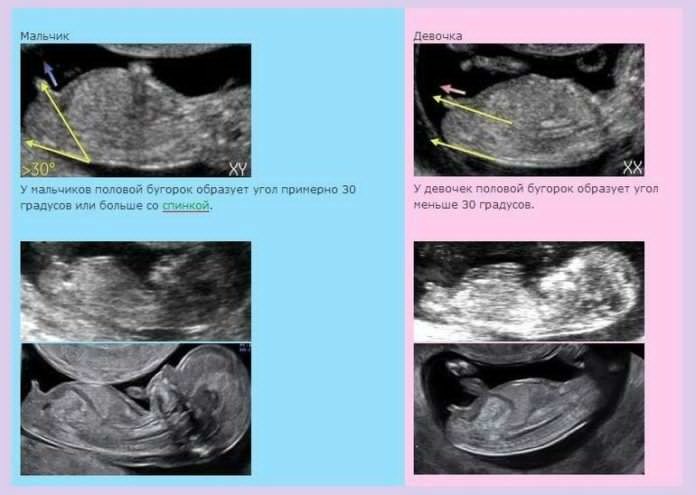

До скрининга 13дней,мы развлекались как могли: предполагали, гадали и просто пытались почувствовать :)) да прибудет с нами сила, чтобы дождаться :)